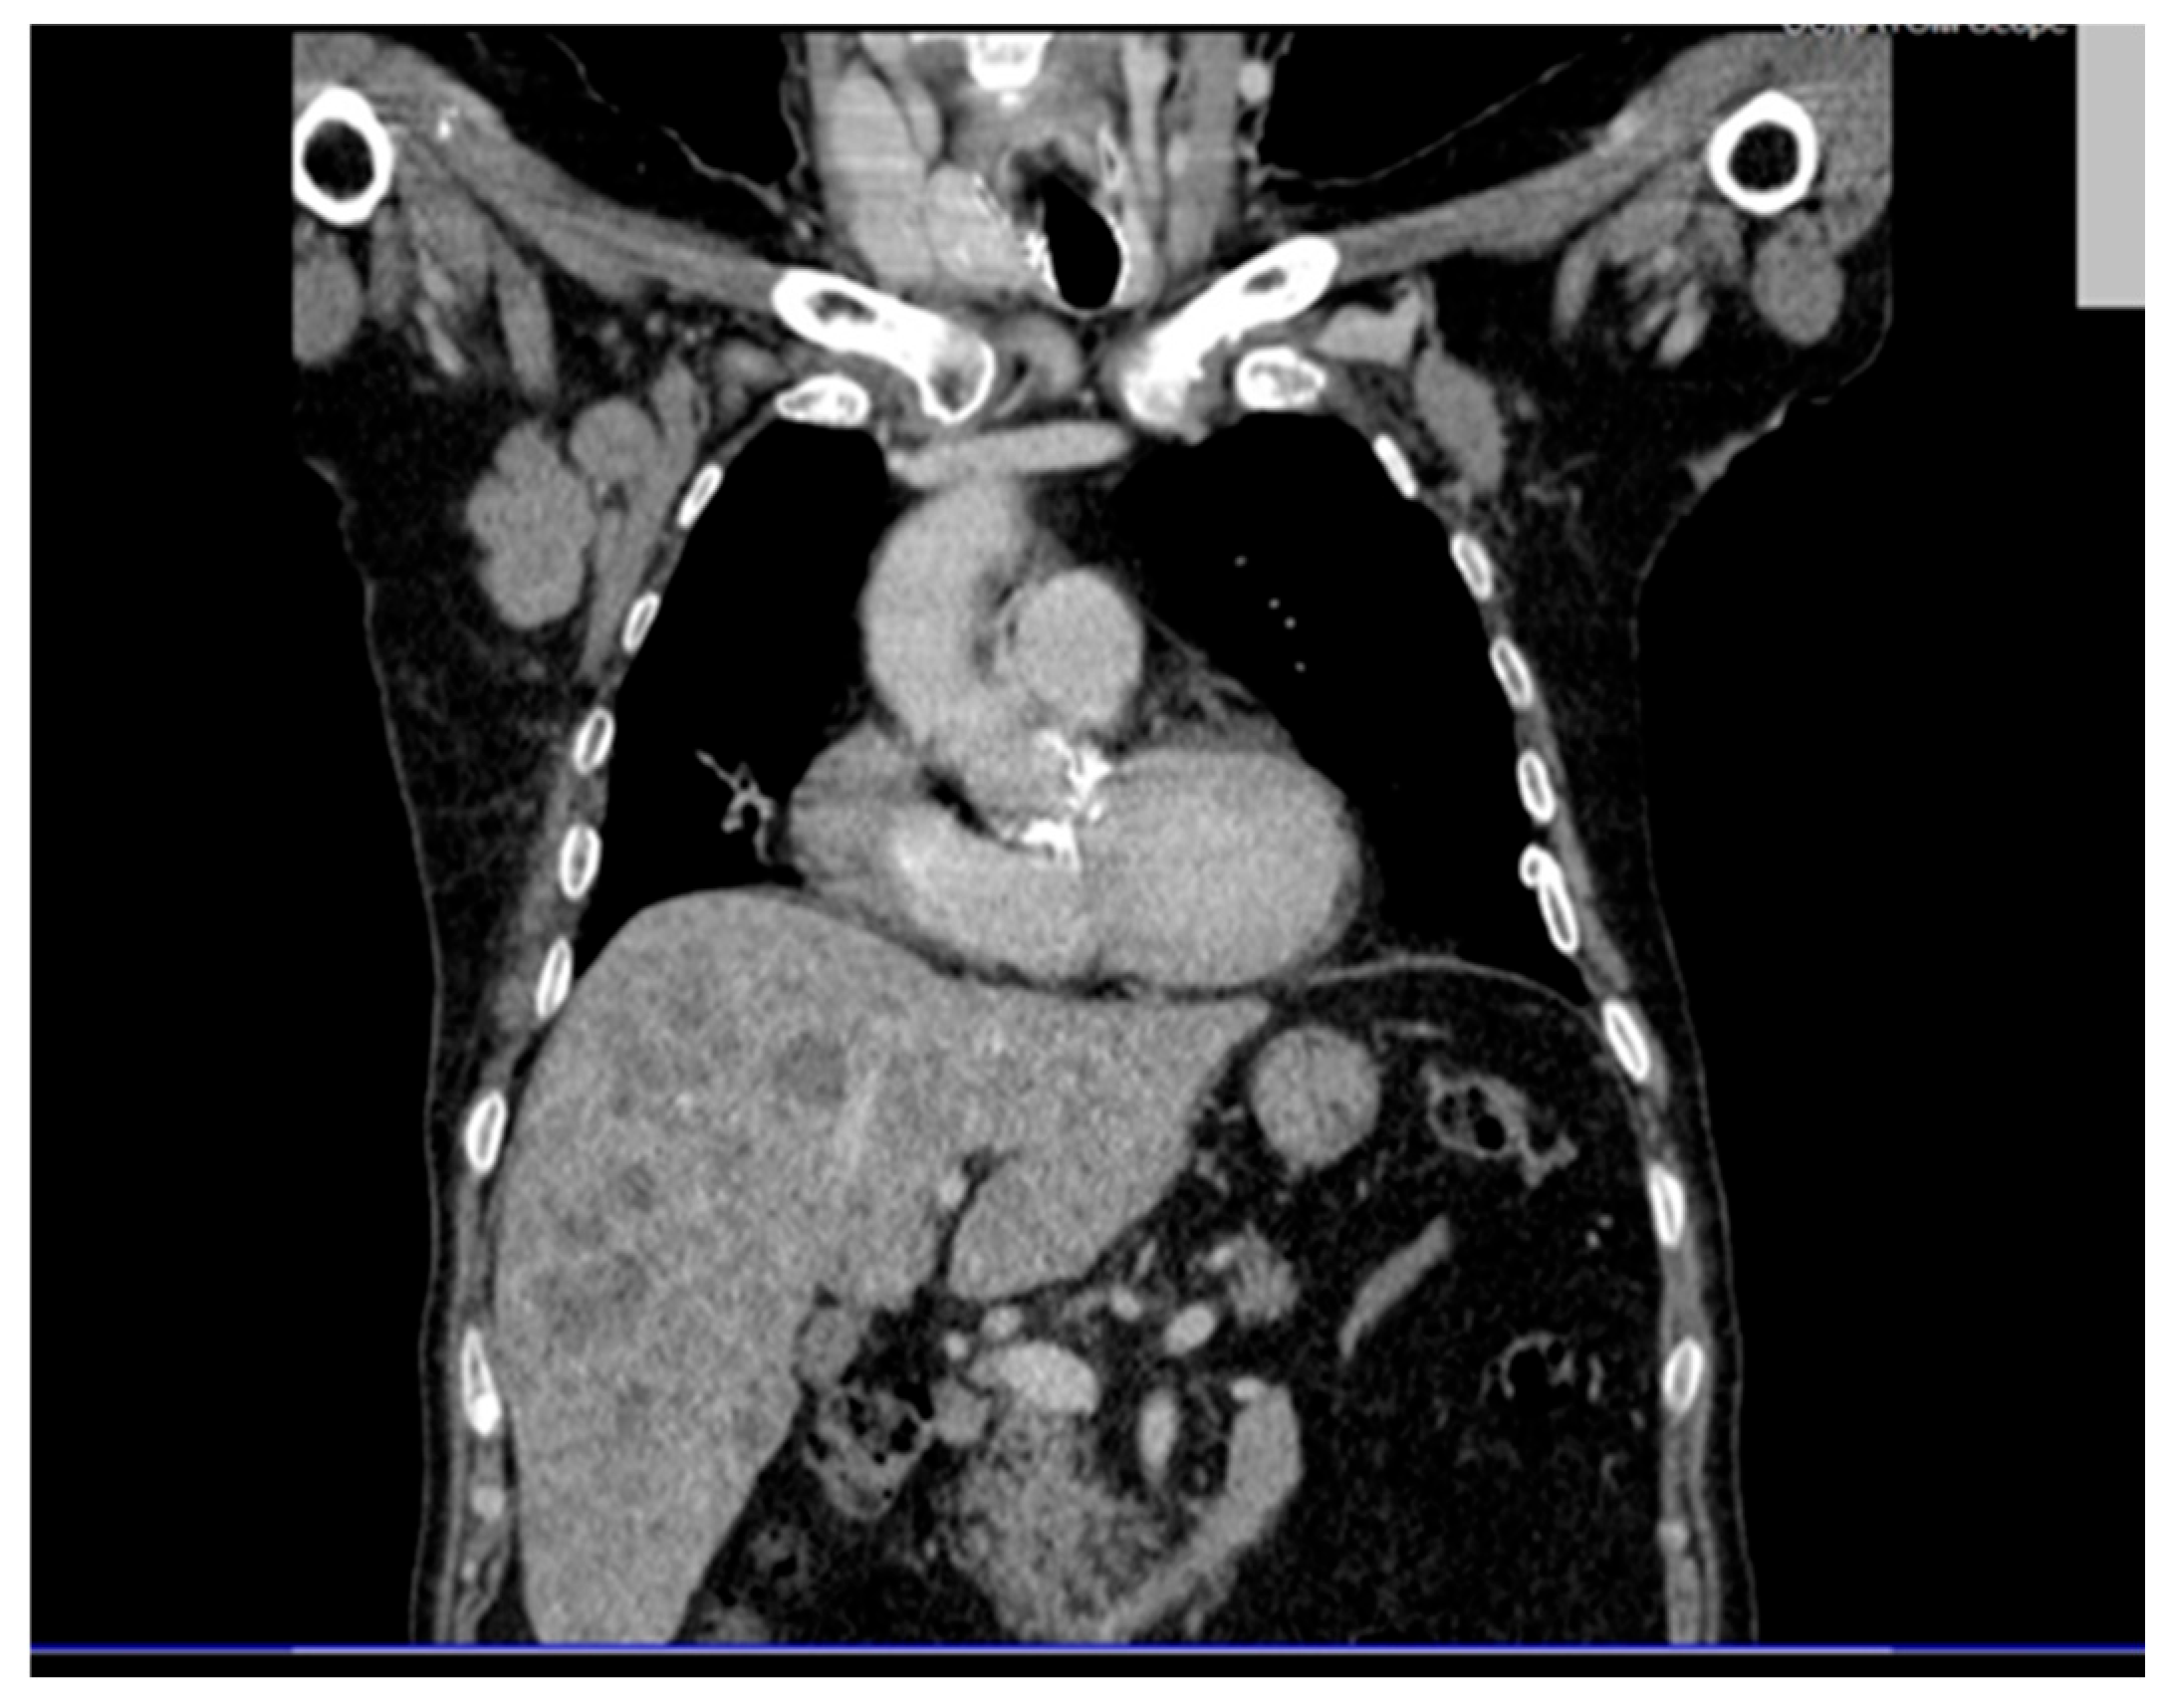

To further investigate, a contrast-enhanced and non-contrast CT scan of the thorax, abdomen, and pelvis was carried out, with the following pathological findings:

Abdominal and pelvic CT revealed hepatosplenomegaly with multiple hypodense, non-enhancing nodular lesions, precaval and hilar lymphadenopathy, bilateral renal cysts (up to 50 mm on the right), a right renal pelvis stone, a right ureteral stent and diffuse osteoporotic changes with vertebral L1 collapse and hyperdense nodular lesions suggestive of possible bone metastases (Figure 3).

Figure 3. Contrast-enhanced abdominal and pelvic CT scan revealing hepatosplenomegaly with multiple hypodense, non-enhancing nodular lesions suggestive of secondary involvement. Bilateral renal cysts, more numerous and larger on the right (up to 50 mm), a 9 mm right renal pelvis stone, and the presence of a right ureteral stent are noted. Diffuse bone structure changes with osteoporotic background and poorly defined hyperdensities are seen, along with L1 vertebral body collapse.